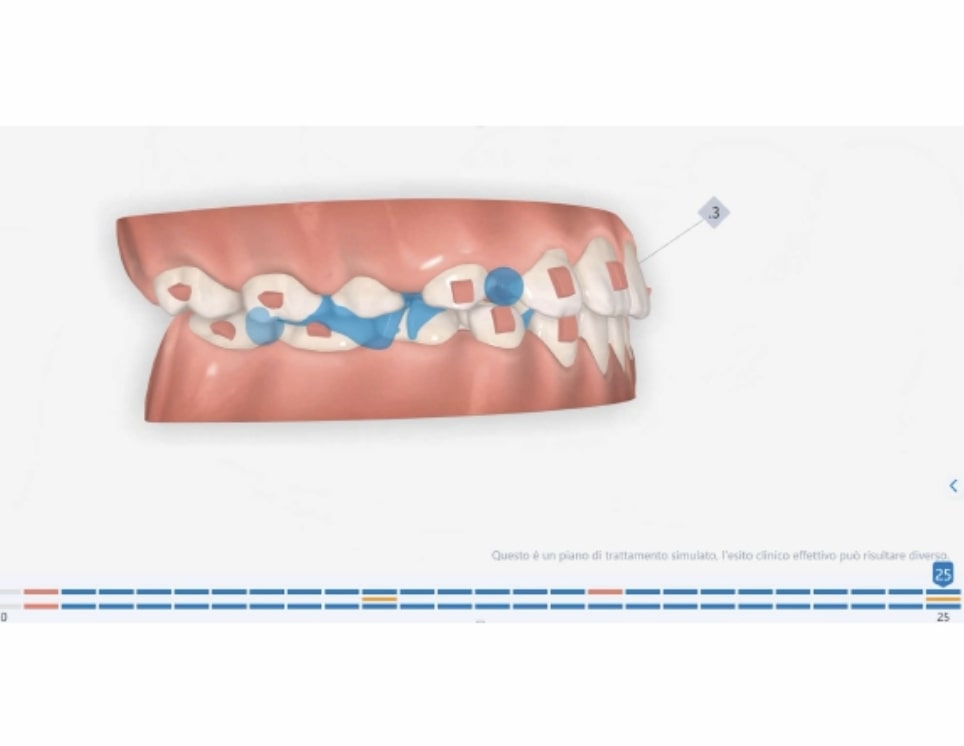

Number of aligners: 25

Malocclusion A6 Correction of Mandibular Retrusion in Growth phase patient | Skeletal Class II | Class II Division 1 malocclusion | Deep bite | Mixed dentition

Protocoles and features A6 Mandibular advancement

- Mandibular Advancement (A6 protocol) + angelBuon for Class 2 Elastics (Night Time)

Treatment setup

Treatment progress